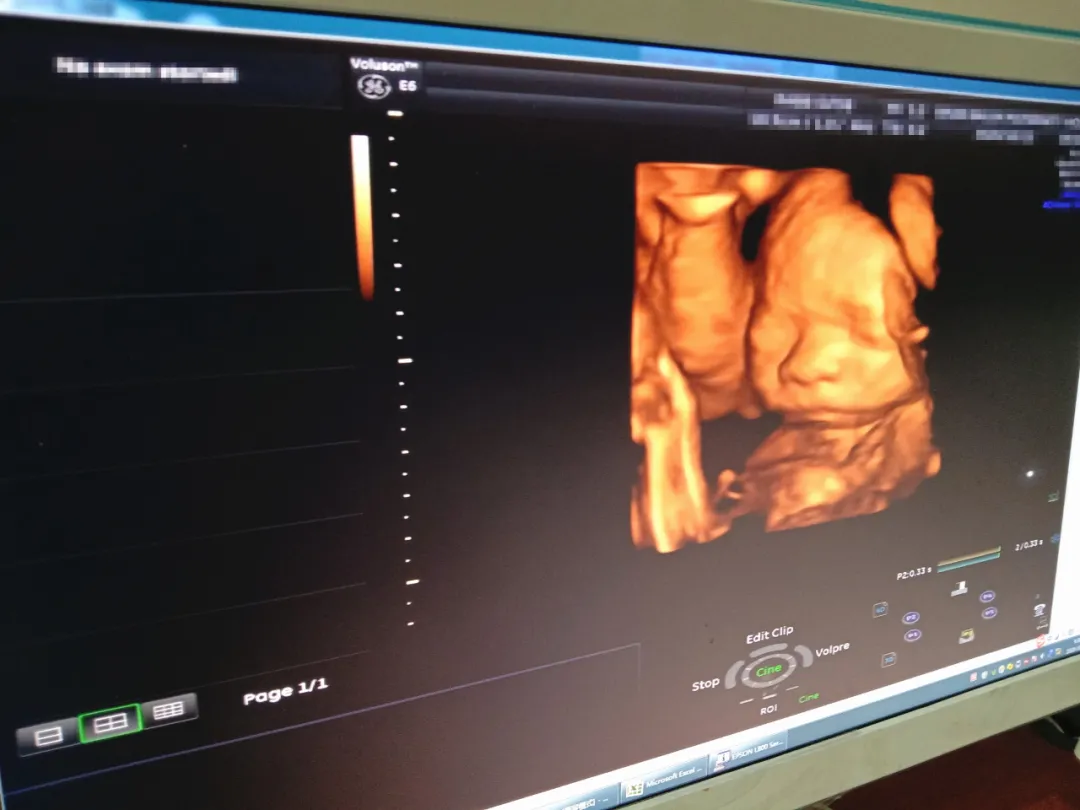

大畸形筛查,也就是我们俗称的“大排畸”、“四维彩超”,孕期的宝妈应该都听过它响亮的大名,这是一项宝妈绝对不能忽视,且一定要做的重要产检项目↓↓↓

因为它可以检查宝宝各器官及外表发育是否正常,排查胎儿是否存在结构缺陷,排除重大心脏畸形,同时还能检查胎儿的生长发育、胎盘情况以及羊水情况,可以说是给宝宝的一次健康大“搜查”。

(1)胎儿头颅:颅骨强回声环、脑中线、侧脑室、后颅窝池:

(2)胎儿脊柱:排列、连续性;

(3)胎儿心脏:显示并观察四腔心切面;

(4)胎儿腹部:观察腹壁、脐带腹壁人口、肝、胃、双肾、膀胱;

(5)胎儿四肢:显示一侧股骨并测量股骨长度.显示一侧脑骨并测量脑骨长度;

(6)胎儿颜面部:双眼眶、上唇皮肤连续性;

(7)动脉多普勒频谱测值。